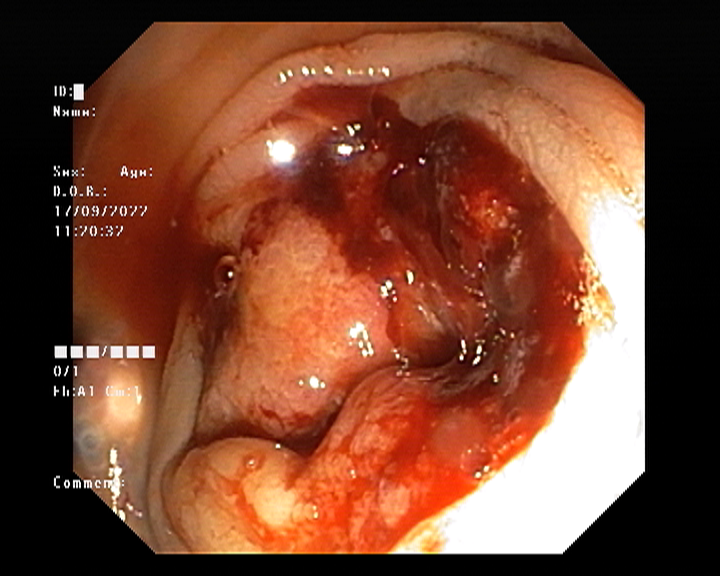

Endoscopy and colonoscopy are safe and accurate procedures used to directly examine the digestive tract and detect the root cause of chronic acidity, GERD, abdominal pain, bleeding, and bowel irregularities. These minimally invasive tests help identify ulcers, inflammation, infections, polyps, strictures, and early cancerous changes.

At Sapphire Gastroenterology Center, modern endoscopic equipment ensures precise diagnosis and, when required, therapeutic intervention during the same procedure. Based on findings, targeted treatment plans are created, including medication, diet guidance, and preventive strategies. Early diagnosis through endoscopy and colonoscopy plays a crucial role in preventing serious complications and improving long-term digestive health.